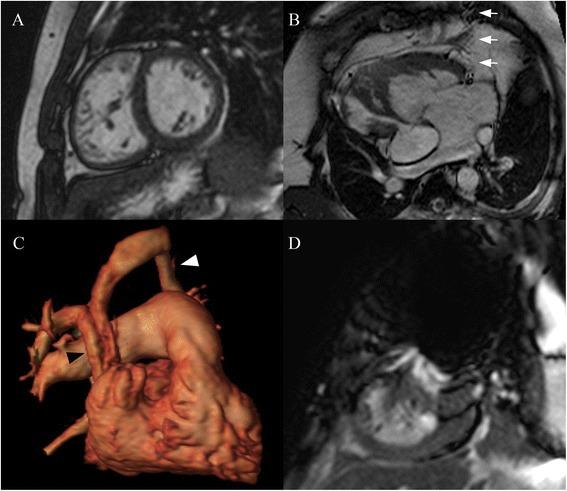

This retrospective, cross-sectional study included all patients ≤18 years old or with congenital heart disease who underwent CMR on an open 1.0 Tesla scanner at two centers from 2012-2014. Indications for CMR and clinical questions were extracted from the medical record. Studies were qualitatively graded for image quality and diagnostic utility. In a subset of 25 patients, signal-to-noise (SNR) and contrast-to-noise (CNR) ratios were compared to size- and diagnosis-matched patients with CMR on a 1.5 Tesla scanner.

A total of 65 patients (median 17.3 years old, 60% male) were included. Congenital heart disease was present in 32 (50%), with tetralogy of Fallot and bicuspid aortic valve the most common diagnoses. Open CMR was used due to scheduling/equipment issues in 51 (80%), claustrophobia in 7 (11%), and patient size in 3 (5%); 4 patients with claustrophobia had failed CMR on a different scanner, but completed the study on open CMR without sedation. All patients had good or excellent image quality on black blood, phase contrast, magnetic resonance angiography, and late gadolinium enhancement imaging. There was below average image quality in 3/63 (5%) patients with cine images, and 4/15 (27%) patients with coronary artery imaging. SNR and CNR were decreased in cine and magnetic resonance angiography images compared to 1.5 Tesla. The clinical question was answered adequately in all but 2 patients; 1 patient with a Fontan had artifact from an embolization coil limiting RV volume analysis, and in 1 patient the right coronary artery origin was not well seen.

Open 1.0 Tesla scanners can effectively evaluate pediatric and congenital heart disease, including patients with claustrophobia and larger body size. Despite minor artifacts and differences in SNR and CNR, the majority of clinical questions can be answered adequately, with some limitations with coronary artery imaging. Further evaluation is necessary to optimize protocols and image quality.